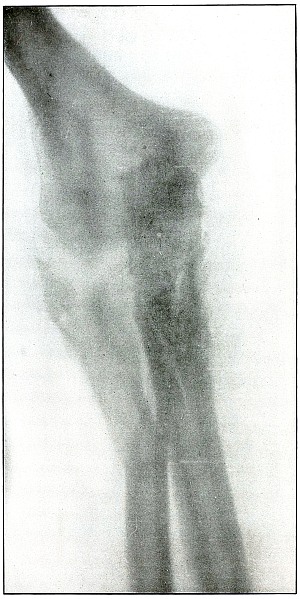

Rifle—Plate 61.

LOWER EXTREMITY.

Gunshot Fracture of the Lower Ends of the Tibia and Fibula.

The course of the bullet was transverse, with the velocity of mid-range.

The fragmentation of the fibula, lying close to the skin, would produce considerable laceration in the wound of exit.

The treatment is conservative. Infection would depend almost entirely upon the integrity of the first dressings and immobilization.

Results should be favorable, with care in subsequent treatment. [Pg 134]